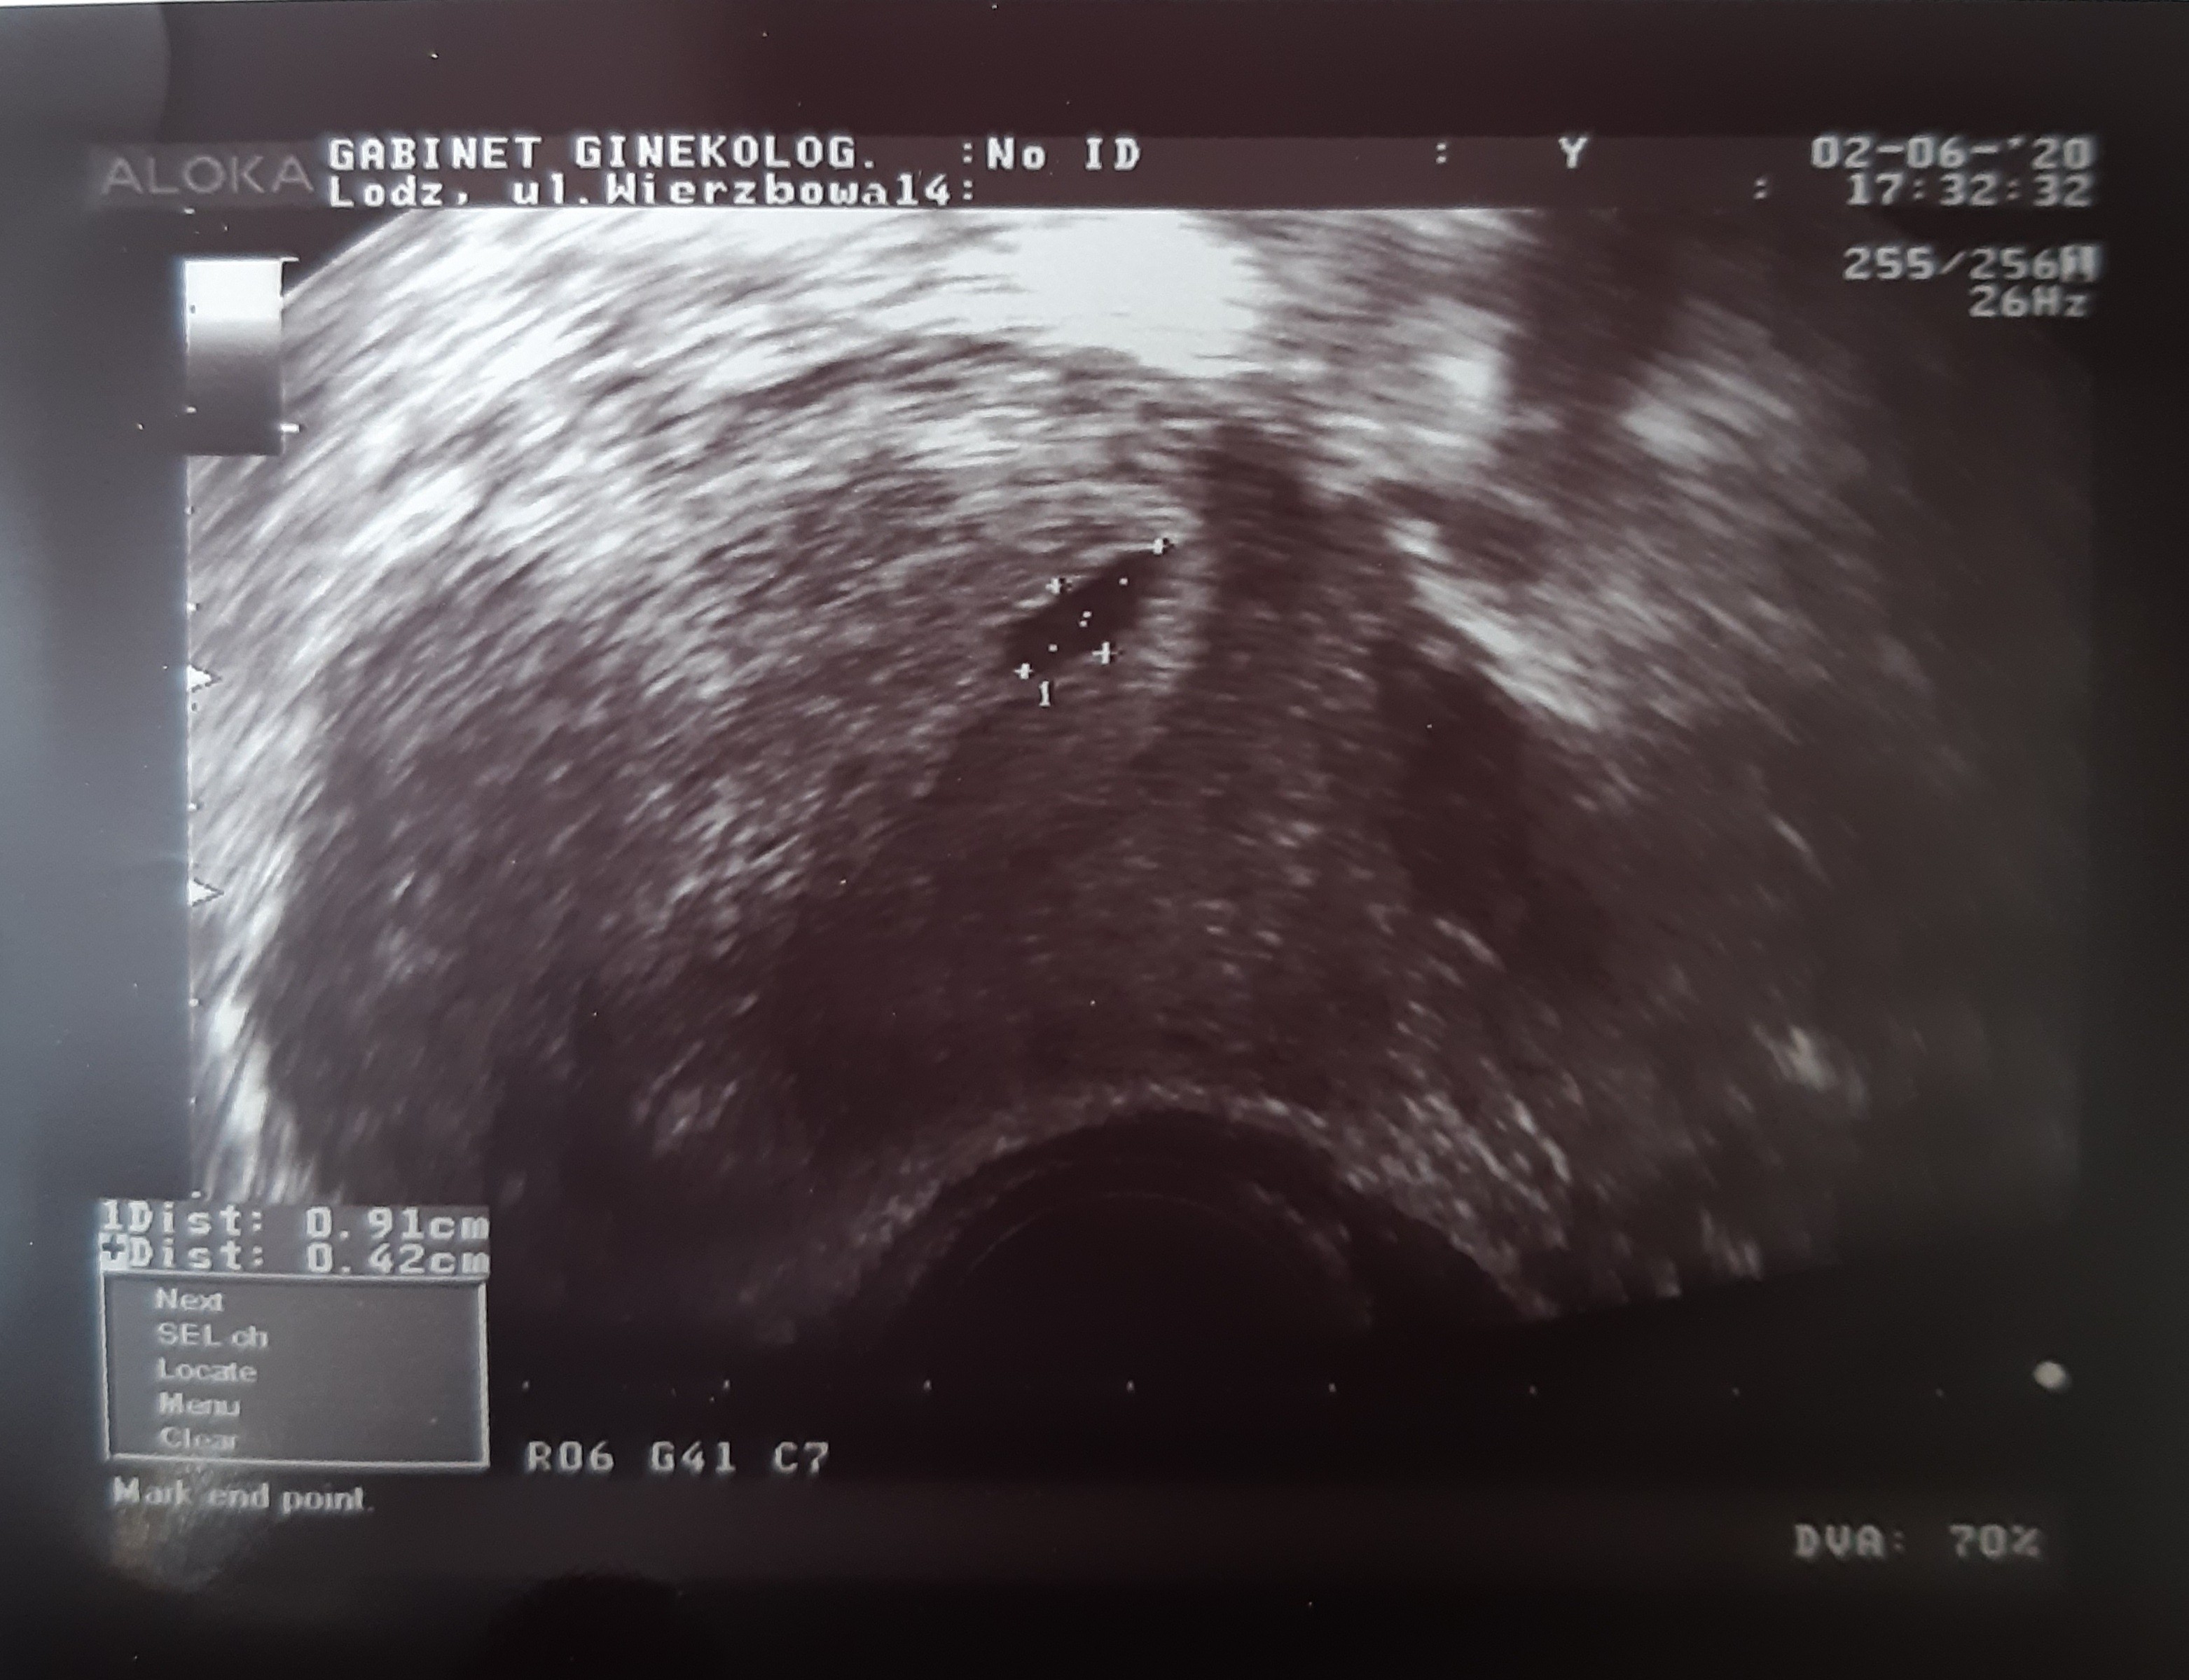

Jestem dziś po pierwszej wizycie.

Według ostatniej miesiączki to jest 5+2 a według USG 4+6 więc nieduża różnica. Widzieliśmy malutki pęcherzyk. Zarodka jeszcze nie.

Na tym etapie jest wszystko w porządku. Mam skierowanie na badania i założona kartę ciąży. Kolejna wizyta za 3 tyg.

Termin na 04.02.2021 😊

Załączam USG ale nic nie widać. Przez chwilkę tylko widziałam 😋

U nas tak to wygląda, mamy ten sam tydzień co Ty 😊